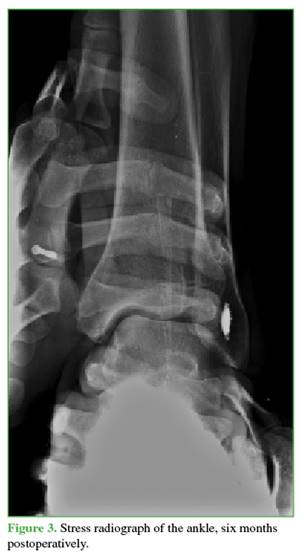

Lateral ankle instability was defined as a talar tilt greater than 10° with respect to the tibial plateau, or more than 5° compared to the contralateral extremity on stress radiographs.9

Patients with ankle trauma were evaluated with conventional radiographs. Once fractures were ruled out, a clinical examination for lateral instability of the tibiotalar joint through varus stress was performed. When clinical suspicion arose, the diagnosis was confirmed with stress radiographs, taken with the patient fully relaxed and with no more than 10° of dorsiflexion to reduce tension on the calcaneofibular ligament. Rearfoot varus stress was applied while stabilizing the distal leg and comparing it to the contralateral, healthy ankle (Figure 1).

All stress radiographs were performed by a single traumatologist specializing in leg, ankle, and foot surgery. The X-ray equipment used was a Pimax model Micro HF 601-33.